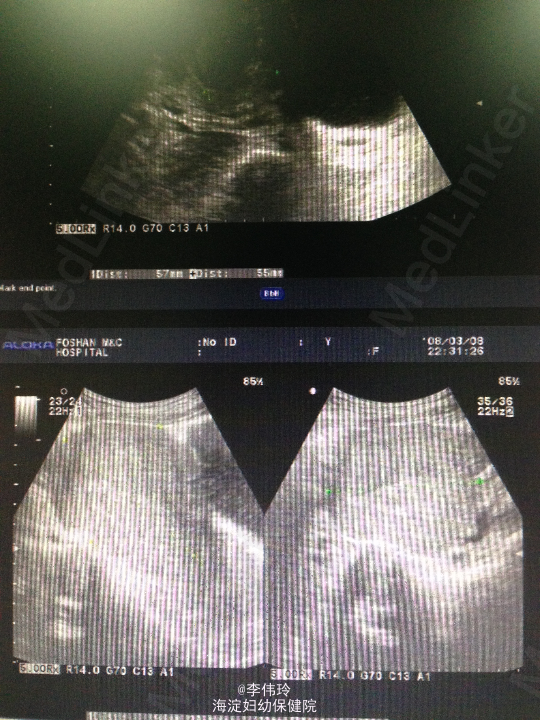

诊断:早孕药流 处理:予口服米非司酮+米索前列醇行药物流产。自然配出胎儿及其附属物,复查B超:子宫增大,宫内膜最厚径2、2cm,回声欠均,宫内残留物并积血可能,肌壁间肌瘤(5.7×5.5cm)。行清宫术,术后预防感染,加强宫缩等治疗。先患者一般情况可。